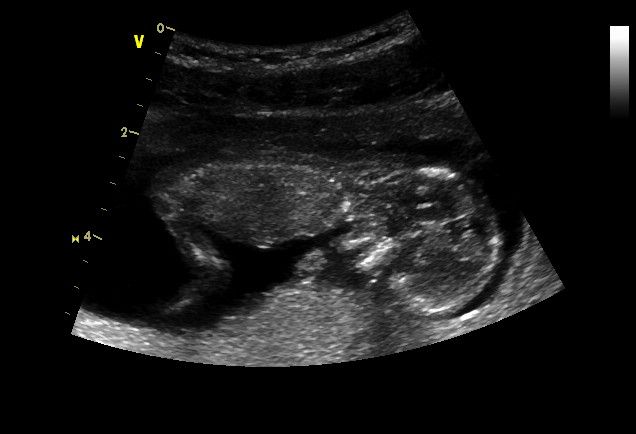

Ahoj holky, tak včerejší screening v Gennetu dopadl dobře, měla sem z toho trochu nervózu, ale nakonec to byl krásný zážitek. Mohla jsem mimi sledovat na velké plazmě jak tam hýbe ručičkama, nožičkama. Paní doktorka všechno změřila, prohlídla orgány, počet prstů, noh, rukou :)). Všechno jak má být. Pouštěla mi i do velkých reproduktorů srdíčko jak krásně bije. No prostě fakt super zážitek. Nazávěr všechny údaje zadala do nějakého programu a ten jí vyplivl výsledek screeningu.Byla to paráda, i slzička mi ukápla. Přikládám fotečku. Prcek byl ale k sondě zády, vůbec se nechtěl ukázat, tak nevím ani pohlaví a fotečka z boku je maximum co prcek ze sebe ukázal

. Stydlín asi.